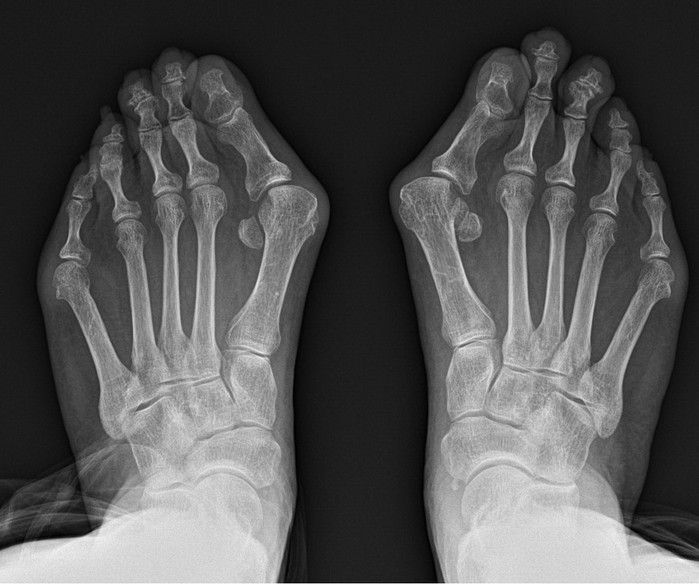

그 대표적인 예로 무지외반증을 꼽을 수 있다. 무지외반증 이란 엄지발가락이 새끼발가락 방향으로 휘며 엄지발가락이 시작되는 관절의 뼈가 돌출되는 질환이다.

그래서 무지외반증은 되도록 빨리 치료하면 좋지만 실제로 보행에 큰 지장이 오기 전까지는 방치하는 경우가 대다수다. 오랜기간 방치하게 되면 수술이 필요하게 되는데, 발은 여러 뼈가 얽혀있는 생각보다 복잡한 부위다. 그래서 환자들은 과연 수술 후 발 모양이 정상으로 돌아올지 그리고 통증은 심하지 않은지 걱정하게 된다.

박 병원장은 돌출 부 내측 한 부위 절개를 통해 교정과정의 부담을 최소화 했다. 변형이 심하거나 양측변형 이라도 엄지뼈를 안으로 밀어 넣어 소위 ‘칼발’로 불리는 교정이 가능하다. 교정이 변형되지 않도록 수술 후 일정기간 핀이나 나사로 고정하는 것으로 수술을 마친다. 수술 과정이 축소되면서 절개창도 기존과 달리 단일화 돼 통증 및 흉터 부담도 최소침습술 만큼 경감됐다.